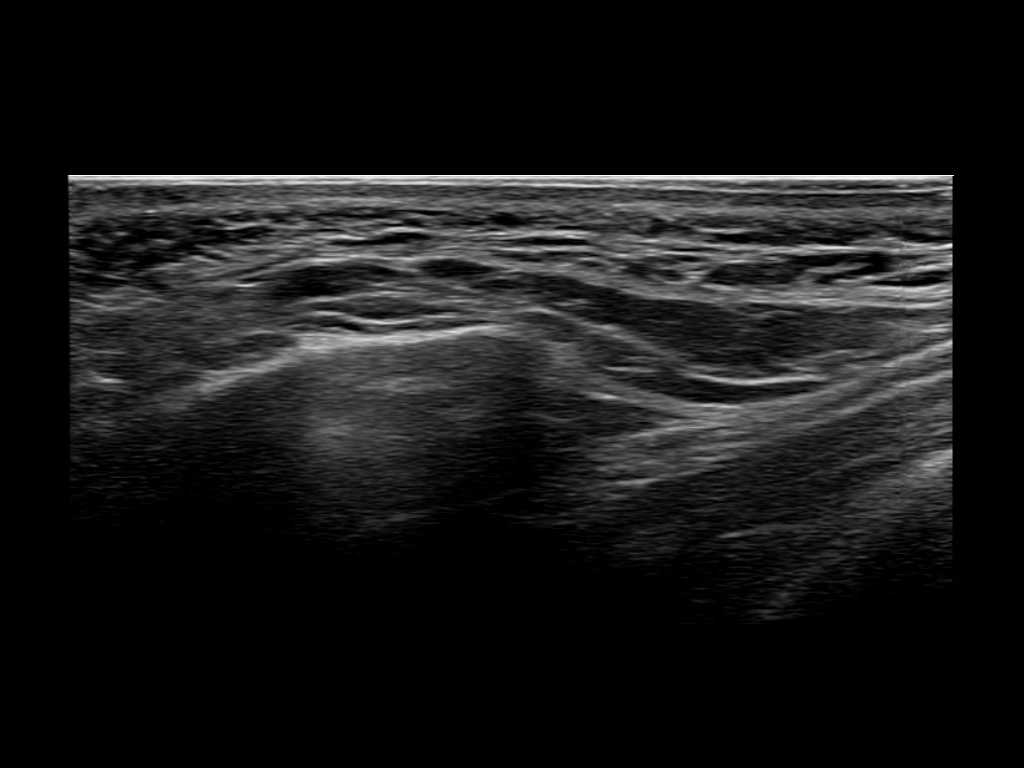

Study the first image to recognize the different layers. If you are sure about the layers, swipe to the second image to view the answer (if applicable).

Hover over an image to view the secondary image or click on the image title for more information.